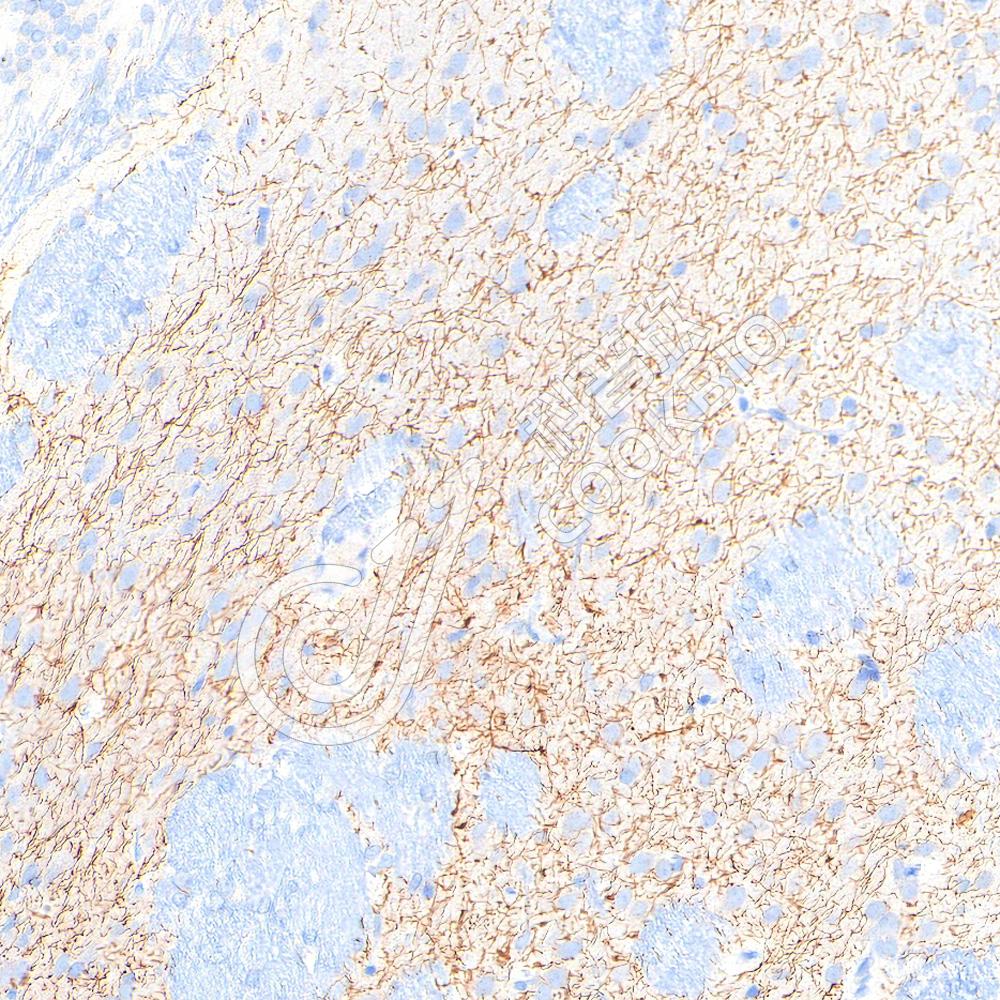

IHC检测Acetylcholinesterase蛋白(货号 K545114).

样品: 小鼠纹状体, 4%多聚甲醛 (货号KSG1101) 固定12-24小时.

抗原修复: 柠檬酸抗原修复液(干粉, pH 6.0) (KSG1201), 高压锅均匀喷气计时2分钟.

—抗: 1: 800稀释, 4℃ 孵育过夜.

二抗: S-vision免疫组化多聚二抗(山羊抗兔),即用型 (货号KB3906), 室温孵育20分钟.

样品: 大鼠海马区, 4%多聚甲醛 (货号KSG1101) 固定12-24小时.